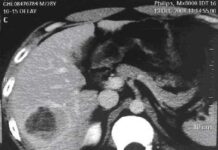

Ung thư gan: có thể chữa được nếu phát hiện sớm

Ung thư gan là nguyên nhân gây tử vong chính trên toàn thế giới với hơn 600.000 ca tử vong mỗi năm. Ở...

Cảnh giác dấu hiệu ung thư gan

Ung thư gan là bệnh ung thư phổ biến thứ hai trên thế giới chỉ sau ung thư phổi, triệu chứng thường gặp...